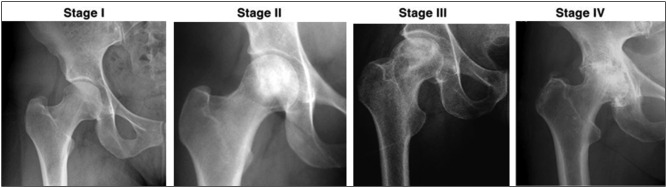

Background: Sickle cell disease (SCD) has a high prevalence in Sub-Saharan Africa. Avascular necrosis (AVN) of the femoral head is a devastating complication of SCD. Early presentation and diagnosis can be treated with hip-preserving procedures, resulting in good outcomes. Late presentations will require more complicated treatment procedures, such as hip replacement. A good knowledge of the clinical presentation and severity of the disease will aid in early detection and clinical management. This study was designed to establish the age and sex distribution, severity, and stages of AVN in SCD patients at Korle-Bu Teaching Hospital.

Materials and methods: This was a cross-sectional study of SCD patients referred to the orthopaedic clinic with AVN of the femoral head. An evaluation form was used to assess the patient's age, sex, genotype, and clinical symptoms. Hip X-rays were obtained to assess the severity of the disease. Chi-square tests were used to determine the association between demographic variables' data and AVN.

Results: Most patients were in the 31- to 50-year age group and presented with profound and limiting clinical features and advanced features on X-rays (stages 3 and 4 of the disease). There was a statistically significant association between the radiological stage of disease and clinical symptoms (limping, difficulty climbing stairs, and hip abduction).

Conclusion: The patients mostly presented with severe disease both clinically and radiologically and will require complex surgical procedures including hip arthroplasties. Clinicians at primary care centres need to look out for early signs so that they can refer them for treatment.